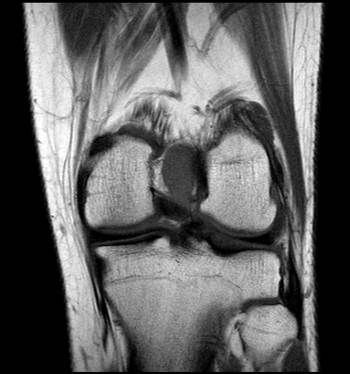

La RNM de rodilla izquierda informa de lesión de 2´6 cm de diámetro en cisura intercondílea entre ambos ligamentos cruzados, con sospecha de sinovitis villonodular pigmentada focal (ver imagen 1).

Imagen 1: RNM de rodilla izquierda donde la flecha señala tumoración en cortes coronal y sagital.